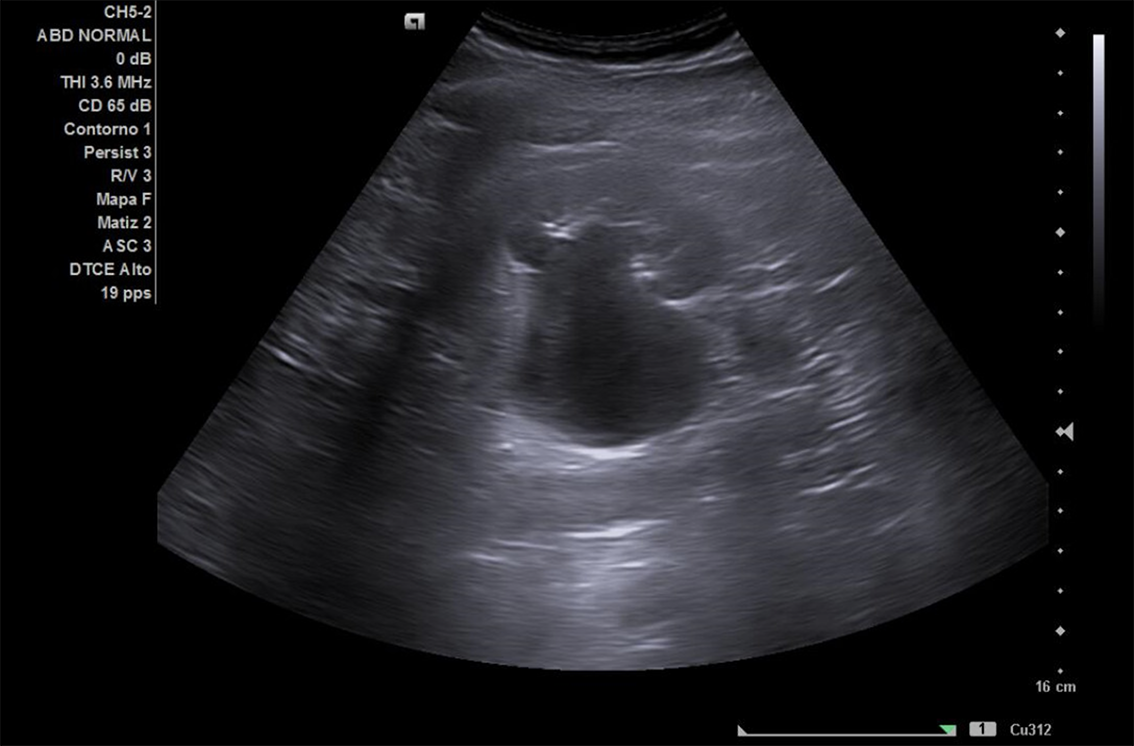

Se realiza ECO POCUS en la que se aprecia riñón derecho de morfología y tamaño normal. Riñón izquierdo con hidronefrosis grado III. A nivel de vejiga, bien replecionada se aprecia masa a nivel de pared izquierda adyacente a unión ureterovesical de 1.8 x 2,7 cm Ausencia de jet izquierdo.